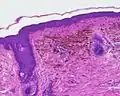

- Imagen histológica de un naevus coeruleus cellularis (2x)

- Forma maligna de un nevus azul. Todos los cortes histológicos están en la tinción hematoxilina-eosina.